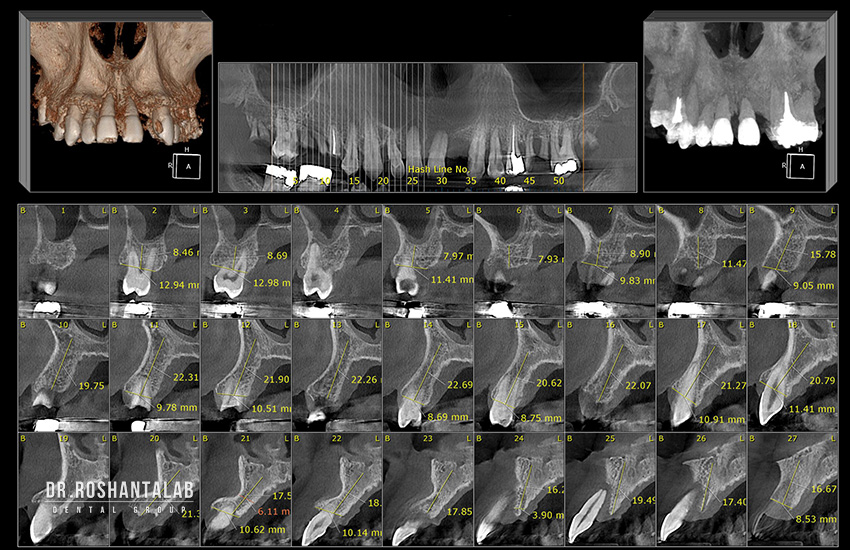

ایمپلنت دیجیتال یک روش انقلابی در دندانپزشکی ایمپلنت است که از فناوری‌های پیشرفته دیجیتال برای برنامه‌ریزی، طراحی و اجرای کاشت دندان استفاده می‌کند. این روش شامل ابزارهایی مثل تصویربرداری سه‌بعدی با پرتو مخروطی (Cone Beam Computed Tomography یا CBCT)، نرم‌افزارهای طراحی کامپیوتری (CAD/CAM)، اسکنرهای داخل دهانی و چاپگرهای سه‌بعدی است. برخلاف ایمپلنت‌های سنتی که به تصاویر دوبعدی و روش‌های دستی وابسته هستند، ایمپلنت دیجیتال کل فرآیند را خودکار و دقیق می‌کند.

در هسته این روش، فیکسچر تیتانیومی (پیچ ایمپلنت) قرار دارد که در استخوان فک کاشته می‌شود، سپس اباتمنت (اتصال‌دهنده) و روکش سرامیکی یا زیرکونیایی روی آن نصب می‌گردد. طبق اطلاعات Mayo Clinic، نرخ موفقیت ایمپلنت‌های دیجیتال به ۹۸ درصد می‌رسد، زیرا برنامه‌ریزی کامپیوتری موقعیت دقیق ایمپلنت را تعیین می‌کند و ریسک آسیب به عصب‌ها یا سینوس‌ها را به حداقل می‌رساند. این روش زمان جوش خوردن استخوان (osseointegration) را از ۳-۶ ماه به ۲-۴ هفته کاهش می‌دهد، زیرا قرارگیری دقیق‌تر باعث واکنش بهتر بافت می‌شود.

این مرحله با یک جلسه مشاوره آغاز می‌شود. دندانپزشک تاریخچه پزشکی بیمار را بررسی می‌کند (بیماری‌های زمینه‌ای مثل دیابت، داروها و عادات مثل سیگار). سپس، اسکن CBCT انجام می‌شود که تصاویر سه‌بعدی دقیق از فک بالا و پایین، موقعیت عصب‌ها، سینوس‌ها و تراکم استخوان ارائه می‌دهد. این اسکن فقط 10 تا 14 ثانیه طول می‌کشد اما اطلاعاتی معادل صدها عکس دوبعدی می‌دهد. در کلینیک دکتر روشن‌طلب در گیلان، نتایج اسکن بلافاصله در نرم‌افزار CAD/CAM بارگذاری می‌شود تا شبیه‌سازی سه‌بعدی ایجاد شود.